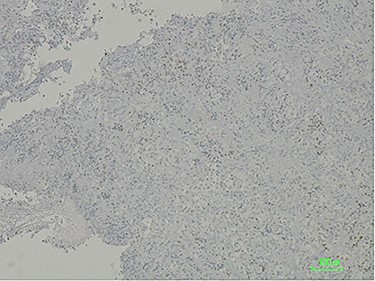

The histologic examination revealed a poorly differentiated adenocarcinoma, with a negative CDX2 and positive PAX8 immunostaining, hence compatible with a secondary lesion of endometrial origin (Figs 3 and 4).

Immunostaining positive for PAX8 suggesting a tumour of gynaecologic origin based on the patient’s past medical history.

To this day, despite direct invasion being quite common, there have been very few reports of duodenal metastasis of malignancies originated in distant organs. Lung, renal, melanoma and colorectal cancer have sporadic reports of duodenal involvement [8, 9]. When identified on endoscopy, they frequently present as ulcerated lesions that can cause GI bleeding or gastric outlet obstruction. This finding is consistent with the endoscopy’s macroscopic description of the duodenal lesion and our patient’s clinical presentation. Immunohistochemistry provided the diagnosis after confirming its non-lower GI tract origin and gynaecologic related epithelial structure (positive for cytokeratin 7, negative CDX2 and positive PAX8 immunostaining) [3, 10].